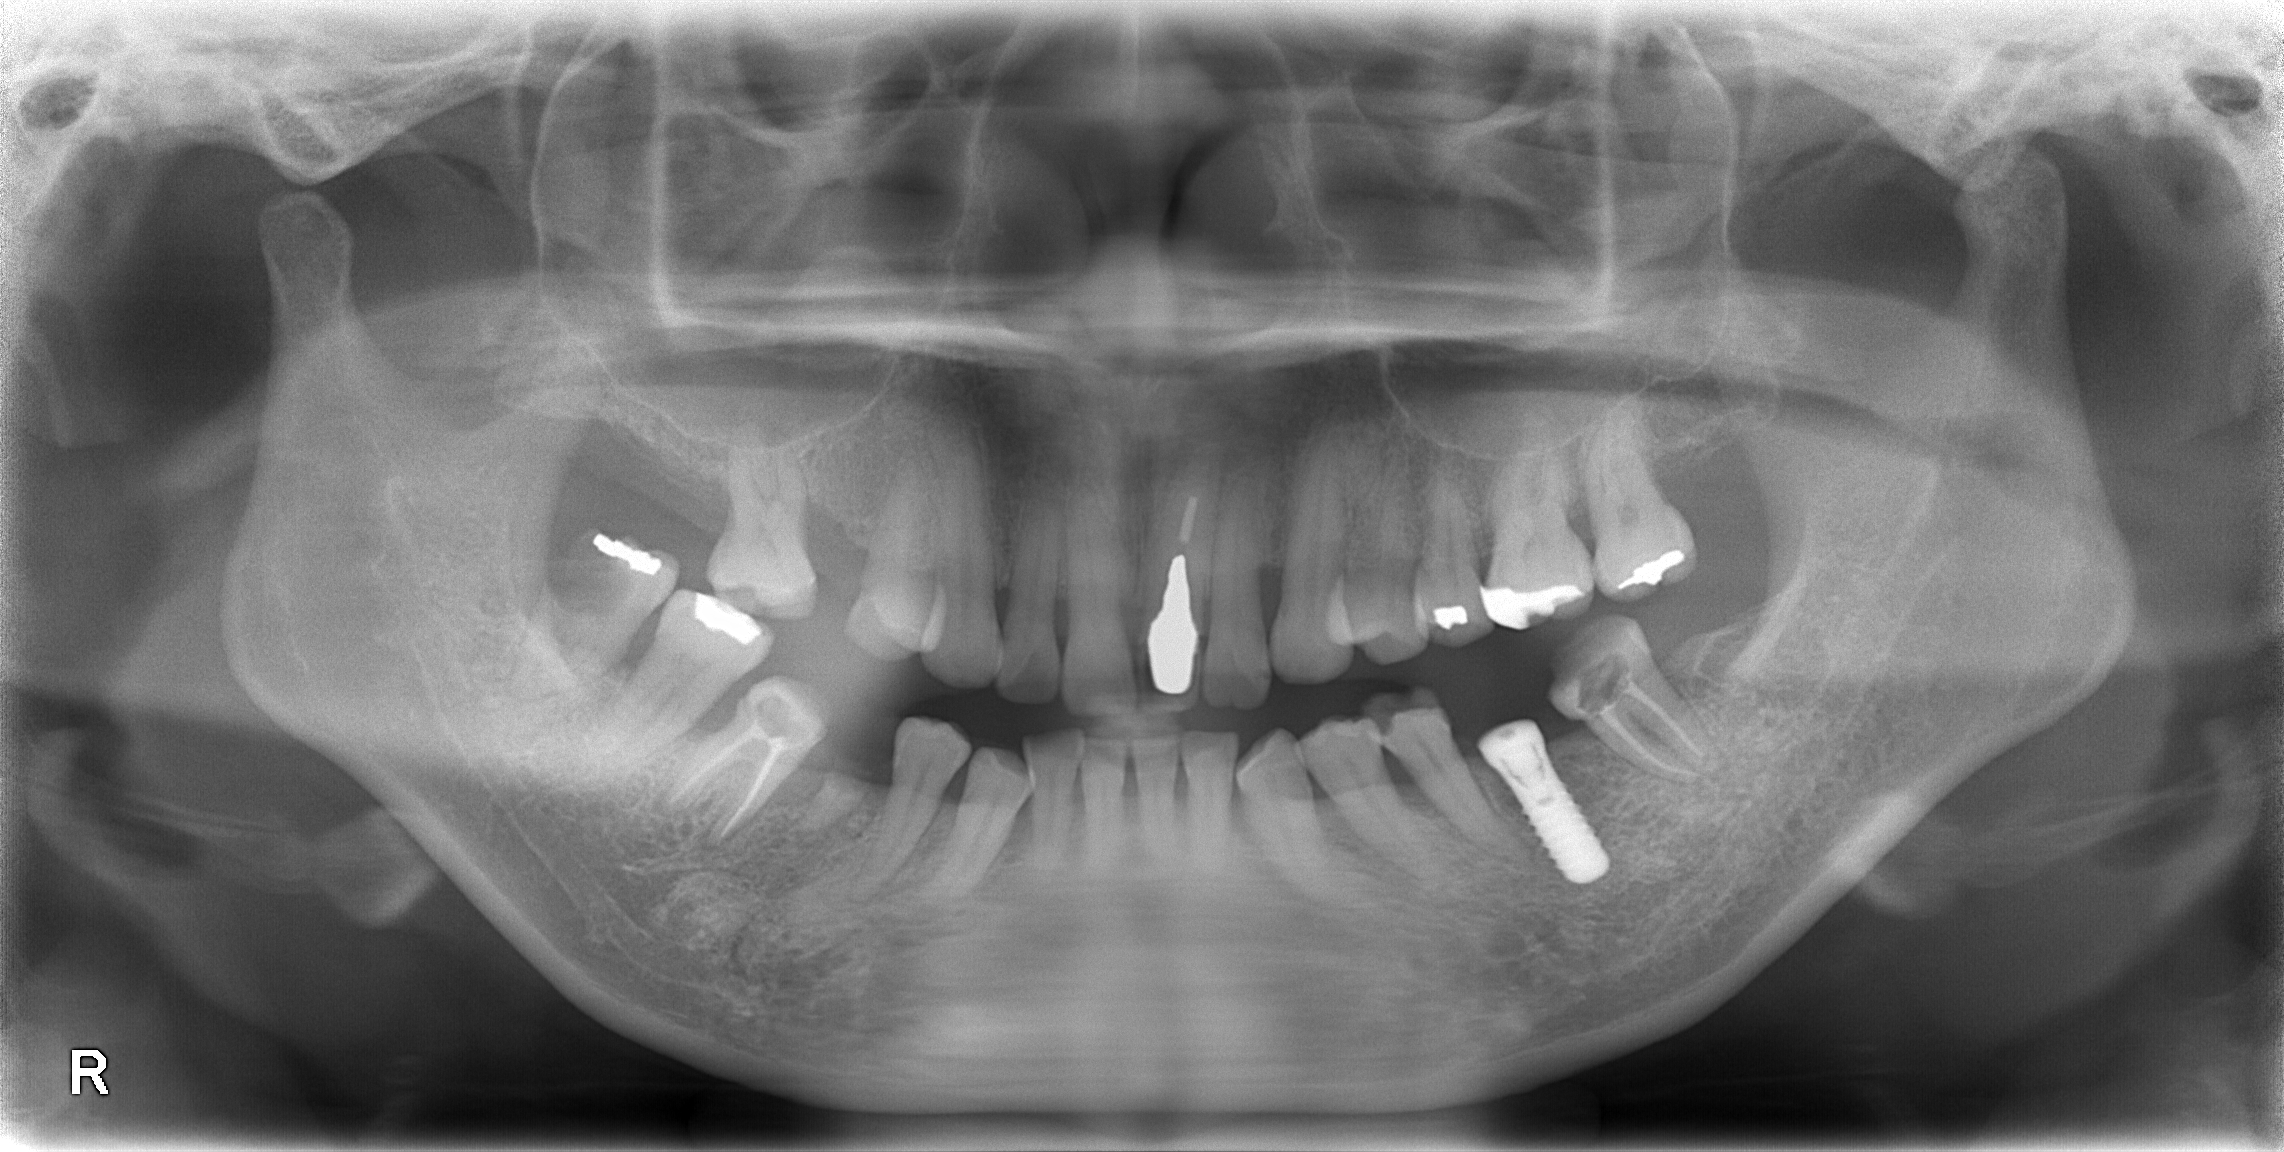

本日もインプラント手術行いました。

画面向かって右下のインプラントです!

手術時間30分、術中痛みもなく終了しております。

当院では、院長が多数のインプラント経験を有しており、このように短時間で術後も痛みが少なくなるよう最小限の歯茎しか切開を行いません。この工夫を凝らすことで、術後の痛みや腫脹を最小限にすることができます!